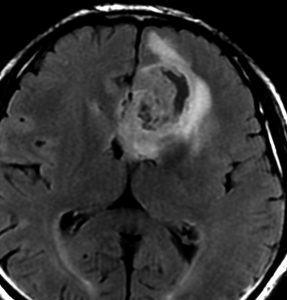

expanding, solid 固形腫瘍的なもの

壊死ではない「のう胞」を伴い,ガドリニウムで強く増強されます。グレード 4 (膠芽腫)と間違えるようなものです。しかし,のう胞はありますが中心壊死がありません。

腫瘍を大部分摘出できるので,積極的な摘出術をして,手術後には放射線化学療法を加えます。この例では,手術後の放射線治療計画の領域が狭ければ,60グレイを使用できる部位です。